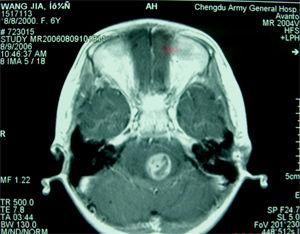

血管网状细胞瘤是一种脑血管性肿瘤。后颅窝是最主要的病变部位。血管网状细胞瘤好发于30~40岁的成年人,男性稍多于女性。如果一个或多个中枢神经系统血管网状细胞瘤, 伴发

视网膜血管瘤

和内脏病变(通常为胰和/或肾脏肿瘤或囊肿),则称为希-林氏病(VHL)。枕部疼痛、头晕、呕吐和运动失调是常见表现。如伴有视网膜血管瘤,可因出血导致视力下降。血管网状细胞瘤的主要治疗手段是手术治疗。手术全切除预后良好。肿瘤残余易局部复发。